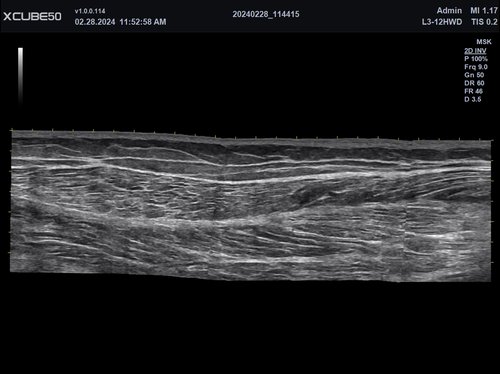

• MSK / Bewegungsapparat

• L3-15H (3-15 MHz) für Ultraschalluntersuchungen in den Bereichen Gefäße, Weichteile, Bewegungsapparat (MSK)

• L3-12H WD (3-12 MHz) für Ultraschalluntersuchungen in den Bereichen Gefäße, Weichteile, Bewegungsapparat (MSK), Pädiatrie

Die ausgefeilte parallele Beamforming-Technologie X + Fit ermöglicht durch das Senden, Empfangen und Verarbeiten großer Datenmengen in hoher Geschwindigkeit eine Verbesserung von Kontrast und Gleichmäßigkeit für eine hervorragende Auflösung.